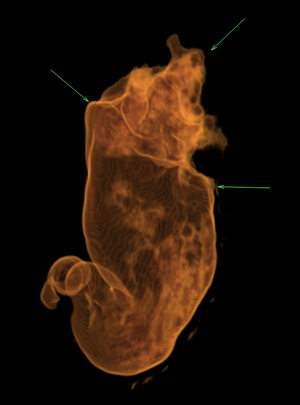

КТ-пневмогастрография – уникальный метод визуализации минимальных опухолей желудка при компьютерной томографии, основанный на раздувании желудка (газообразующей смесью). На выполнение этой методики получен патент сотрудником нашего отделения.